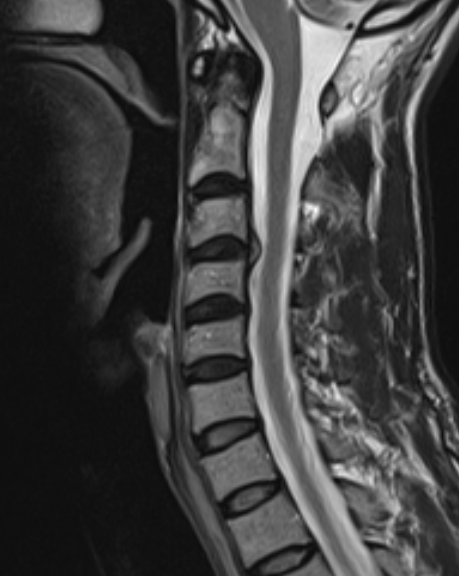

Cervical disc herniation